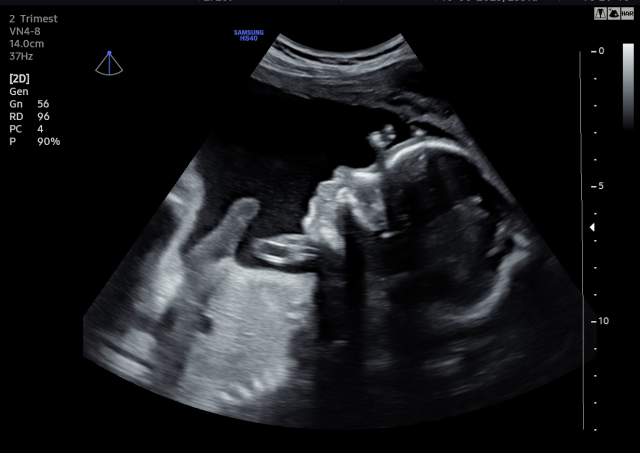

¡La ecografía 5D es una imagen en tres dimensiones y en tiempo real, como la 4D, pero en la que el tratamiento de las imágenes en el ordenador permite suavizar las texturas, modificar el color de la imagen y aplicar un foco de luz desde diferentes ángulos de forma que se crean luces y sombras y esto le da una imagen más real.

La Ecografía 5D incorpora un procesamiento más avanzado que optimiza la iluminación, la textura y la profundidad de la imagen, logrando una representación más clara y uniforme del bebé. Gracias a estos ajustes, los rasgos faciales y los movimientos se aprecian con mayor naturalidad, reduciendo imperfecciones visuales propias de otras modalidades y ofreciendo una imagen final más definida y comprensible para las familias.